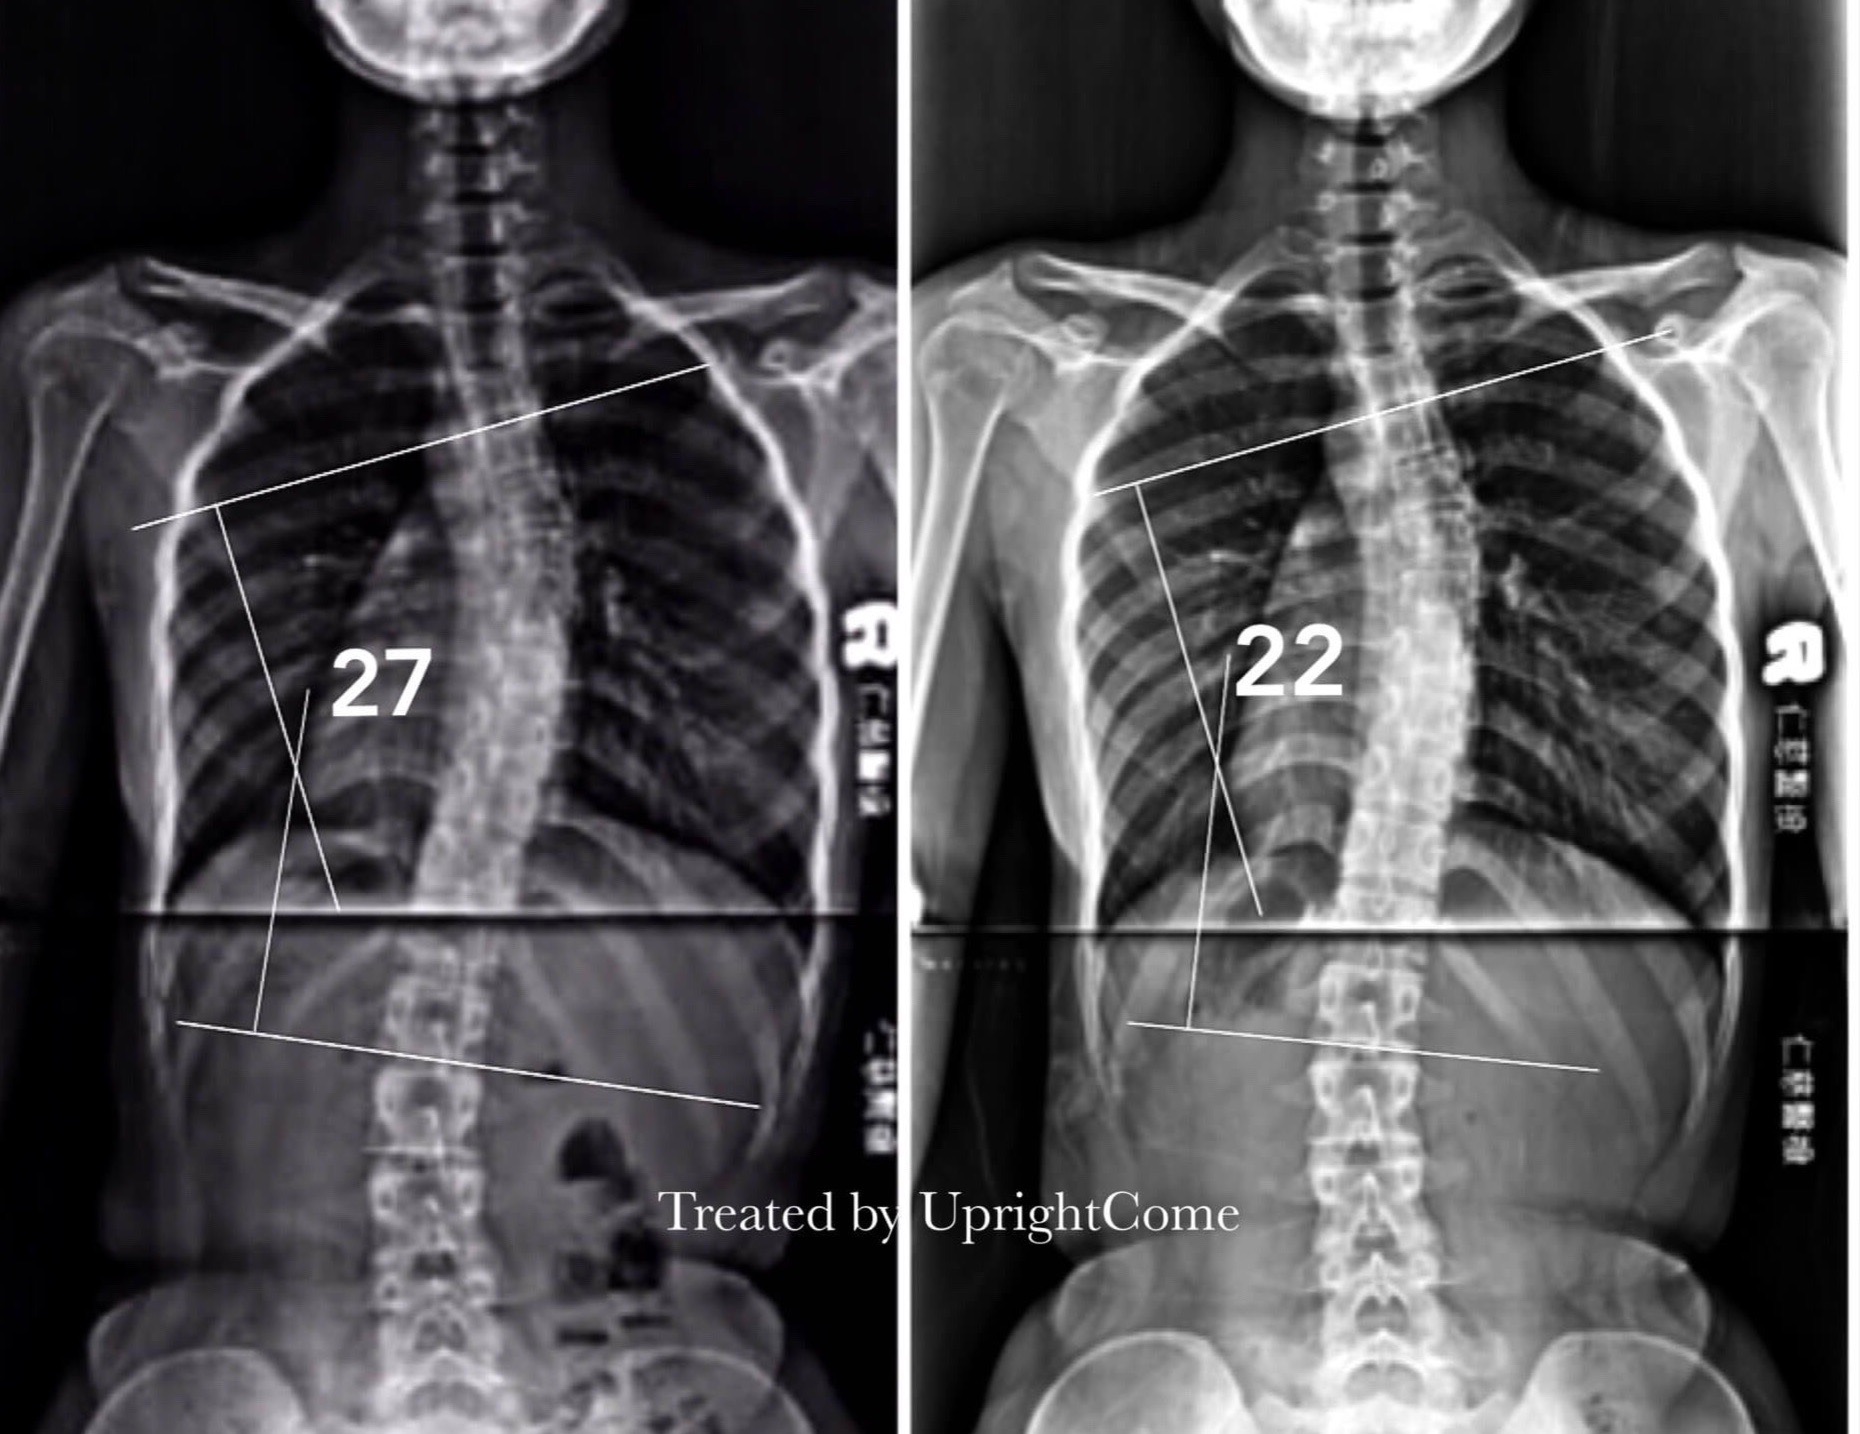

Case 15, 17 years old, 27° Cobb

![脊椎側彎患者經過側彎矯正治療後,胸椎側彎角度由27度減少到22度。]()